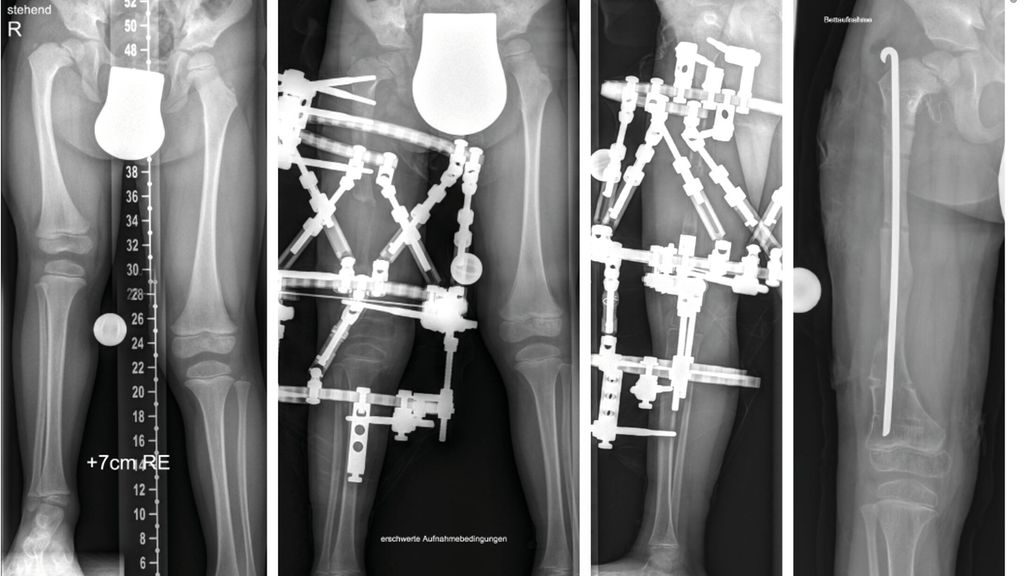

Der kongenitale Femurdefekt ist eine der spannendsten und komplexesten angeborenen Fehlbildungen in der Kinderorthopädie und in der klinischen Präsentation sehr vielgestaltig. Während auf den ersten Blick die Verkürzung des Beins/des Femurs augenscheinlich ist, sind es die assoziierten Veränderungen an Hüfte und Kniegelenk, welche die Therapie herausfordernd machen und vor einer Verlängerung adressiert werden müssen.

Zu den angeborenen Längsdefekten der unteren Extremität zählen neben dem kongenitalen Femurdefekt (CFD) die Fibulahemimelie (FH) und die Tibiaaplasie/-hemimelie. Der Femurdefekt reicht von einer milden Verkürzung des Femurs bis zu seinem fast vollständigen Fehlen, und auch die Fibulahemimelie kann sich von einer milden Verkürzung des Unterschenkels bis zu einer massiven Verkürzung mit schweren Veränderungen am Sprunggelenk präsentieren. Der CFD und die FH kommen fast immer gemeinsam vor, wobei die meisten Fälle eine klare Dominanz der einen oder anderen Pathologie zeigen und die sekundäre Deformität sich oft nur durch minimale Veränderungen an Knochen oder Gelenk präsentiert. Die Tibiaaplasie/-hemimelie ist oft mit Syndromen mit zusätzlichen Fehlbildungen oder Duplikaturen an Hand und Fuß verbunden. Diese Form ist mit einer Inzidenz von 1:1000000 sehr selten.